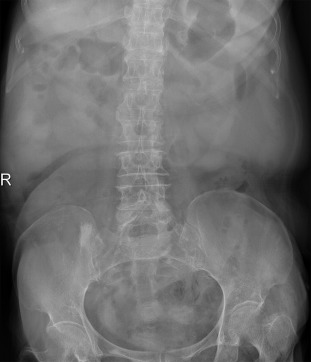

(A) Transverse view of abdominal computed tomography shows multiple outpouching ...

(A) Transverse view of abdominal computed tomography shows multiple outpouching structures (arrows) along sigmoid colon with adjacent fat stranding. (B) Coronal view of abdominal computed tomography shows significant pneumoretroperitoneum (arrow) and pneumoperitoneum (arrowhead).